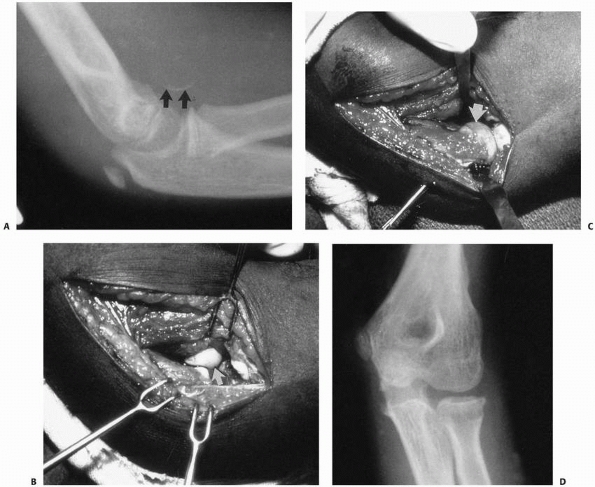

![]() |

FIGURE 15-1 A. Injury film of a 7-year-old with an undisplaced fracture of the lateral condyle (small arrows). Attention was drawn to the location of the fracture because of extensive soft tissue swelling on the lateral aspect (white arrows). B.

Because of the extensive soft tissue injury, there was little intrinsic stability, allowing the fracture to become displaced at 7 days (arrow). |

FIGURE 15-25 Fracture of the capitellum. A. Osteochondral fracture of the capitellum in an 8-year-old girl. Note the small fleck of bone (arrow), which indicates possible osteochondral fragment. B. Intraoperative photograph shows the size and origin of the fracture fragment from the lateral humeral epiphysis. C. Intraoperative photograph after fragment reduction into the bed of the capitellum. D.

Healed fracture with articular congruity, restoration of cartilage space, and no osteonecrosis. (From Drvaric DM, Rooks MD. Case report. Anterior sleeve fracture of the capitellum. J Orthop Trauma 1990;4:188, with permission.) |